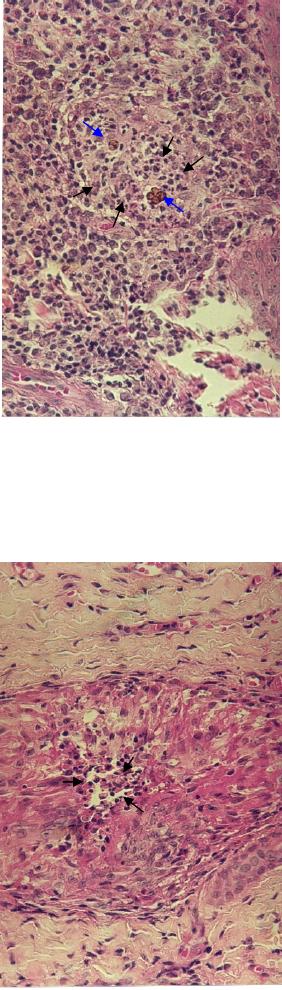

Resgatando o conceito e classificação da inflamação granulomatosa, encontramos

relatado em várias doenças infecciosas, principalmente e inicialmente na hanseníase, uma

visão interessante sobre as formas de granulomas: o de granulomas polares. Neste estudo

(107), também se revela que existe uma confusão sobre definições de tipos de granulomas

em várias doenças granulomatosas, e que estas diferenças e nuances entre os granulomas

não tem sido muito detalhadas pela maioria dos patologistas. Então, baseando-se em

estudos sobre a inflamação granulomatosa na hanseníase, foi proposta uma classificação

morfológica dos granulomas em tipos polares: tuberculóide e não tuberculóide,

correspondendo a dois extremos da lesão. O tipo polar tuberculóide acompanha a lei de

Jadassohn-Lewandowsky, seu agente etiológico é ausente ou escasso (fagocitose

completa). O tipo polar não tuberculóide não acompanha a lei de Jadassohn-Lewandowsky,

seu agente etiológico é sempre presente ou abundante (fagocitose incompleta). Parece que

esta proposta de definição dos granulomas combina morfologia com atividade funcional de

macrófagos, facilmente observados em exames histopatológicos de rotina com microscópio

31

óptico. E a natureza do agente etiológico e sua virulência e resposta Th1/Th2 também

devem ser avaliadas (107).

Figura 24: Esquema de reação granulomatosa tipo 1 e tipo 2.

Fonte: James & Zumla. The Granulomatous Diseases. Cambridge University Press, 2003.